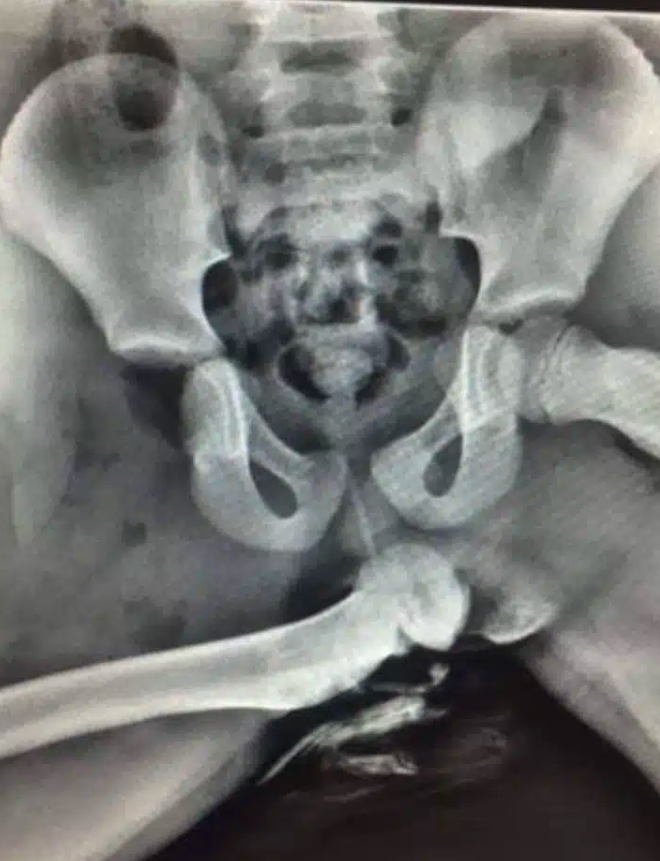

Um policial do Reino Unido compartilhou um raio-X chocante de um passageiro do banco da frente que estava com os pés no painel no momento da colisão.

O fêmur dele simplesmente saiu do lugar onde fica encaixado, que se chama acetábulo, e foi parar na pelve.

Isso pode acontecer porque, quando uma pessoa coloca os pés no painel, o quadril fica em posição de flexão. Com o impacto, o osso da coxa pode se desconectar da articulação.

Mais do que isso, o nervo ciático, localizado atrás da coxa, também costuma ser seriamente danificado, levando a problemas permanentes de movimento na perna.